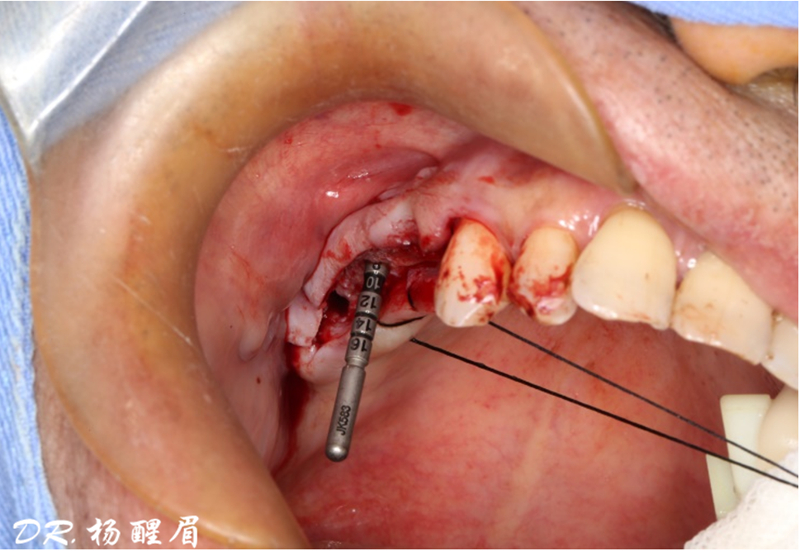

®按照術前方案進行備洞及植體植入

®按照術前方案進行備洞及植體植入,醫(yī)生可以通過屏幕軟件引導對手術中植入點、角度、深度實時追蹤

®對植體深度及方向進行確認